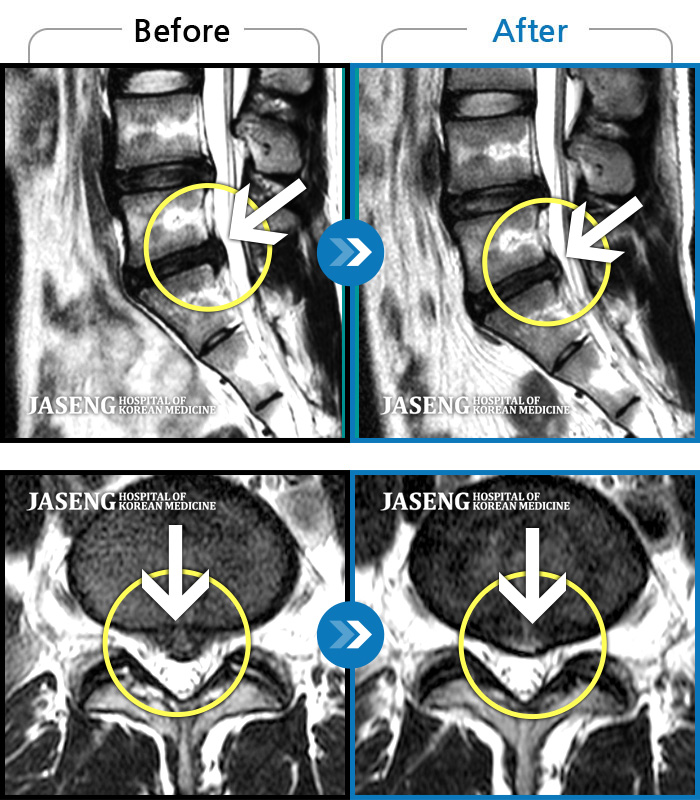

허리디스크

도움받은 사례

강남 · 이남우 원장

허리 통증과 함께 발끝 저림이 1년 이상 되었으며 최근 1-2개월 사이에 증상이 급격히 심해져 우측 다리 앞 뒤가 당기고 힘이 빠져 본원에 내원함

촬영시기

2023.11.20 ~ 2024.08.12